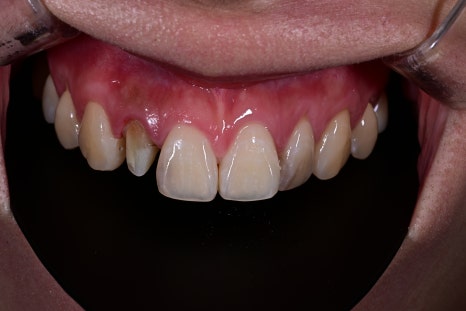

<BEFORE>

<AFTER>

Natural appearance of the gum line restored

A color harmony with the surrounding teeth

Improvement of the sense of incongruity in the front teeth

The response that it “looks like a natural tooth”

was especially impressive.

Front tooth crown treatment is

not just a prosthetic treatment,

but a treatment that changes the image.